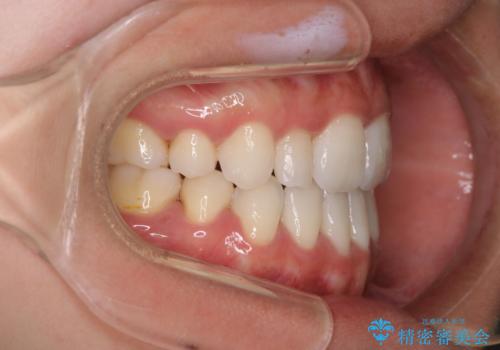

- 口元をさげたいという主訴で来院されました。4番の歯を4本抜歯し、遠心移動とIPRをしました。右上2番が矮小歯のため見た目を重視するならクラウンの提案をしましたが、そのままでの治療を希望されました。

矯正治療の最終段階でスペースクローズにやや時間がかかりましたが、前歯が下がったことで口元の位置も下がりきれいになりました。